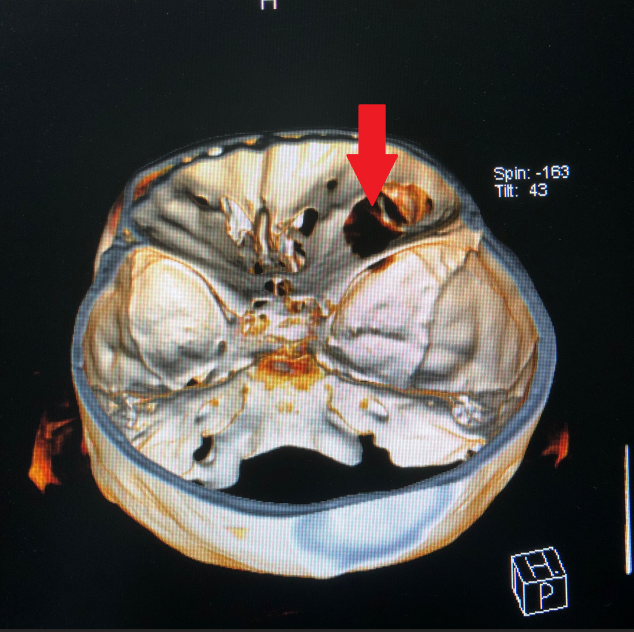

患者王女士,79岁,女性,2周前出现右眼疼痛,眼球突出,随后眼痛逐步加重,右眼视力急剧下降。在当地医院被诊断为眼眶内肿瘤,需手术治疗。但因患者眼眶肿瘤突破眼眶,向颅内生长,手术难度大。患者先后辗转多家医院眼科均无功而返。患者右眼疼痛难忍,最终选择到啄木鸟 寻求最后的帮助。

啄木鸟 神经外科团队接诊后对患者进行了全面检查,诊断为右眼眶肿瘤。因患者肿瘤向颅内生长,颅底及眼眶骨质已完全破坏,传统的手术方式不仅创伤大,更可能因为颅底结构无法完全重建导致患者脑脊液漏,引起颅内感染。神经外科联合眼科进行了手术方式的讨论,根据术中可能出现的各种情况其制定了详细的治疗方案,认真完善术前准备后,于2018年12月24日成功为其开展“完整切除颅内外沟通瘤并颅底眼眶重建修复手术”,手术过程非常顺利,术后患者无视神经损伤,视力较术前明显改善。目前患者已康复出院。